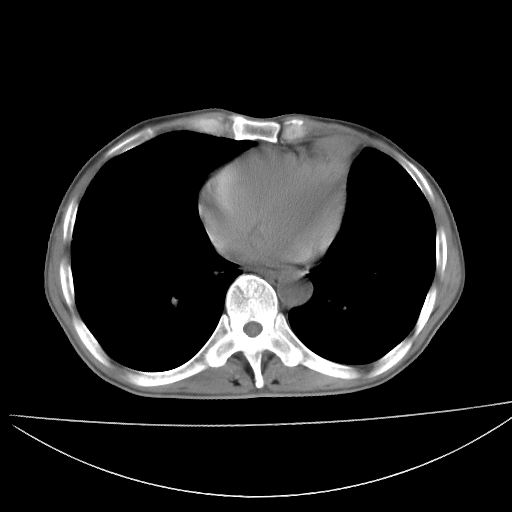

以下是引用杀毒软件在2009-4-28 17:58:00的发言:[br]考虑----左肺慢性肺脓肿形成继发上叶含气不良---抗炎后复查---待排肿瘤所致[br][br][本贴已被 杀毒软件 于 2009-4-28 18:01:26 修改过]